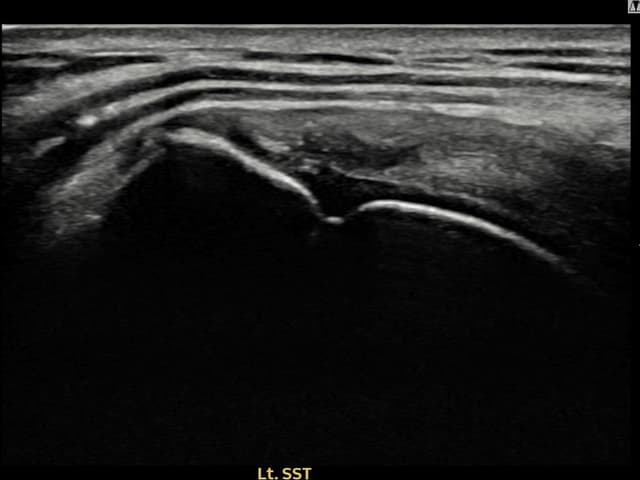

[経過期間: 24.06.04~24.08.12]

[縫縮術] 超音波検査にて左 棘上筋腱 滑液包面側部分断裂(14mm × 7mm (腱厚の約65%欠損))を確認。縫縮術施行後、腱の連続性が回復し、日常生活に復帰されました。